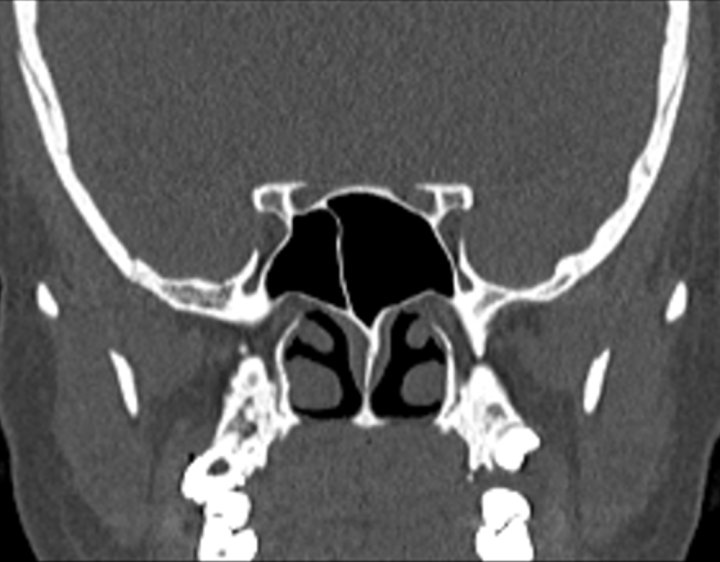

Click any image for labels.